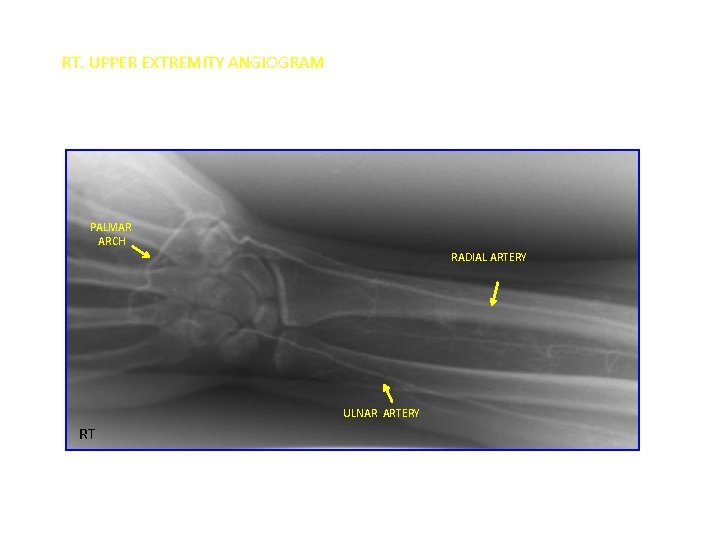

UPPER LIMB VESSELS

RT. UPPER EXTREMITY ANGIOGRAM PALMAR ARCH RADIAL ARTERY ULNAR ARTERY RT